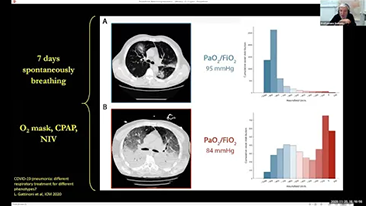

A escolha das configura??es corretas do respirador para o tratamento de pacientes com doen?as do trato respiratĂłrio Ă© uma quest?o muito importante. Como a tarefa de especificar os par?metros do equipamento de ventila??o Ă© inteiramente realizada por um mĂ©dico, o conhecimento e a experiĂȘncia do mĂ©dico na sele??o desses par?metros tem um efeito direto na precis?o de suas decis?es. O paradigma do atendimento de apoio aos pacientes mudou significativamente ao longo dos Ășltimos 20 anos. Atualmente, vĂĄrios modos de ventila??o e ferramentas de apoio Ă decis?o foram desenvolvidos em torno das necessidades clĂnicas para ajudar os profissionais clĂnicos a melhorar a eficiĂȘncia e eliminar os erros nas decis?es clĂnicas.

Integrando oxigenoterapia de alto fluxo, ventila??o n?o invasiva e ventila??o invasiva, os respiradores 3 em 1 da sĂ©rie SV reĂșnem desempenho estĂĄvel, fun??es versĂĄteis e facilidade de uso. Os recursos excepcionais de prote??o pulmonar e as vĂĄrias ferramentas de apoio Ă tomada de decis?es dos respiradores s?o projetados para diminuir o risco de infec??es cruzadas e facilitar a rotina diĂĄria dos profissionais clĂnicos.